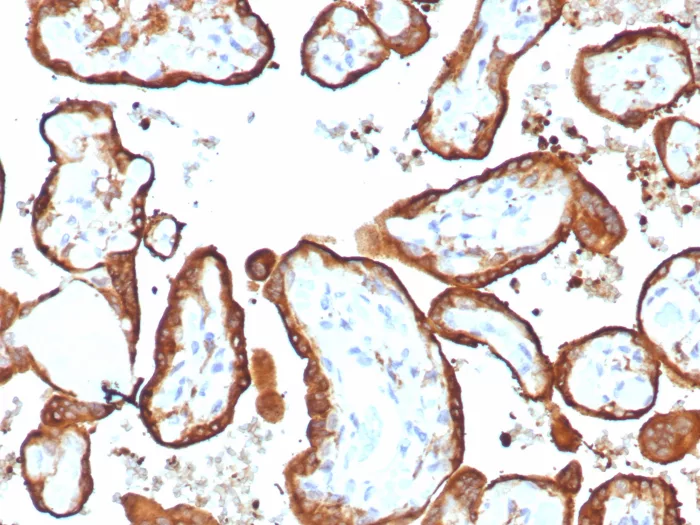

Formalin-fixed, paraffin-embedded human placenta stained with HCG-alpha Rabbit Recombinant Monoclonal Antibody (HCGa/7806R). Inset: PBS instead of primary antibody; secondary only negative control.

Human chorionic gonadotropin antibody (hCG) is a glycoprotein hormone synthesized in syncytiotrophoblastic cells of placenta and in certain trophoblastic tumors. The hormone-specific alpha chains have molecular weights of 13 kDa. HCG is found in moles and choriocarcinoma, chorionic components of germ cell tumors, and syncytiotrophoblast like cells in seminoma/dysgerminoma and embryonal carcinoma. In diagnostic pathology, hCG is a useful marker for classification of germ cell tumors, identification of extragonadal germ cell tumors.